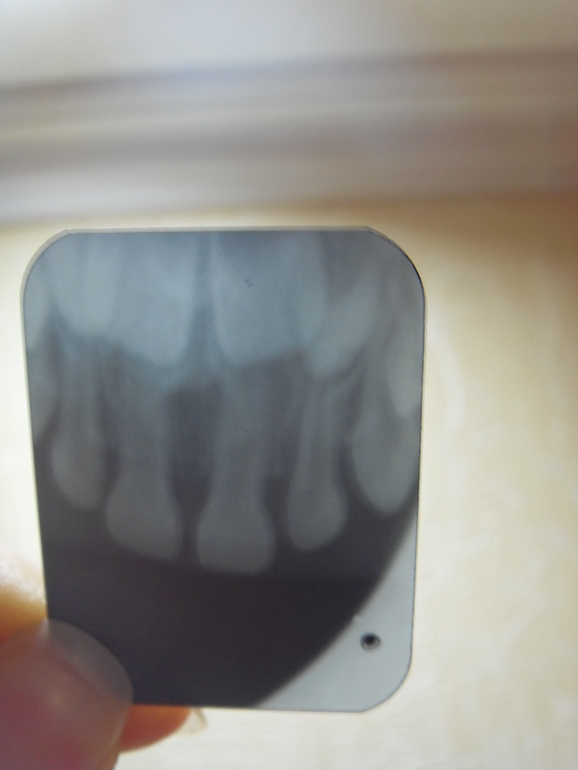

Здраствуйте! Помогите разобраться удалять или нет зубик. В четверг ударилась дочка о пол зубами и пробила губу верхнюю. Десна припухла, кровоточила. В пятницу десна была припухшая, десна над зубиком кровоточила, припухла губа верхняя. К вечеру десна над зубом посинела. Днем была температура 37,4. В субботу температуры не было, губа стухла, но десна кровоточила и так же была посиневшая над зубиком в самом верху. Поехали к дежурному стоматологу в пол-ке, сказали удалять. Поехали в больницу челюс-лицевое отделение, сделали снимок и сказали удалять не нужно, просто наблюдать. Отправляю вам снимок. Зуб повредили 1 правый. Что Вы нам посоветуете?

Здравствуйте.И я не вижу повода для удаления. Наблюдайте.Через месяц повторный снимок сделайте.А синева на десне... Синяк(